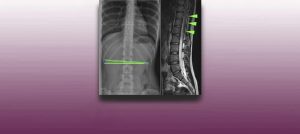

Institut Chiari & Siringomielia & Escoliosis de Barcelona is highly specialized neurosurgical center dedicated to the diagnosis and treatment of spinal and brain disorders, with a focus on the clinical concept of Filum Terminale Disease. Conditions treated include: